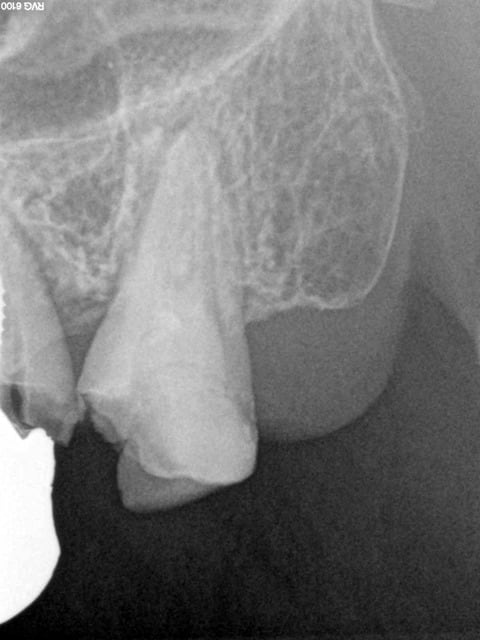

Ah, la France ses endos et soins conventionnels superbes classés au patrimoine de l'humanité.......

Encore un cas plus frais que le précédent, on innove cone sans pate cette fois ci ( ou la moitié du canal en 8 d'obturé. -)))

1 nhq0pn - Eugenol

2 l2h3ce - Eugenol

3 nnbzcw - Eugenol

4 wnkfxu - Eugenol